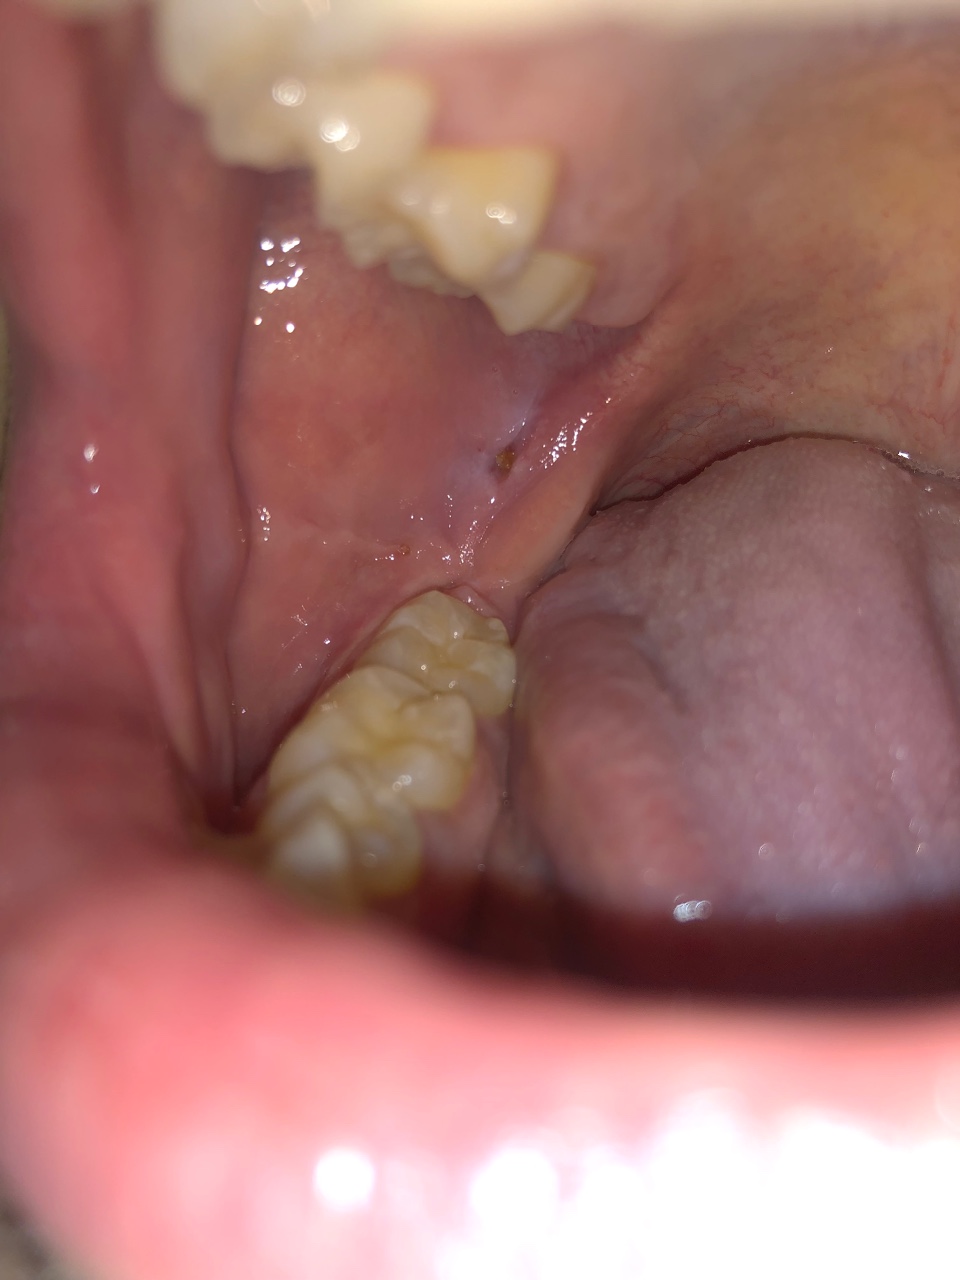

Здравствуйте, пару недель назад появилась боль в десне в области зуба мудрости. Боль была похожа на боль при прорезывания зуба мудрости коих у меня ещё нет. Было затруднительно открывать рот, глотать и был дискомфорт от того что десна касалась с верхним зубом при закрытии рта.

Меньше чем через неделю боль прошла но появилась язвочка в области тремолярного треугольника. Не болит, особого дискомфорта не ощущаю но язва не проходит уже неделю. Подскажите, пожалуйста, связано ли это как-то с зубом мудрости и что посоветуете сделать. Большое спасибо!